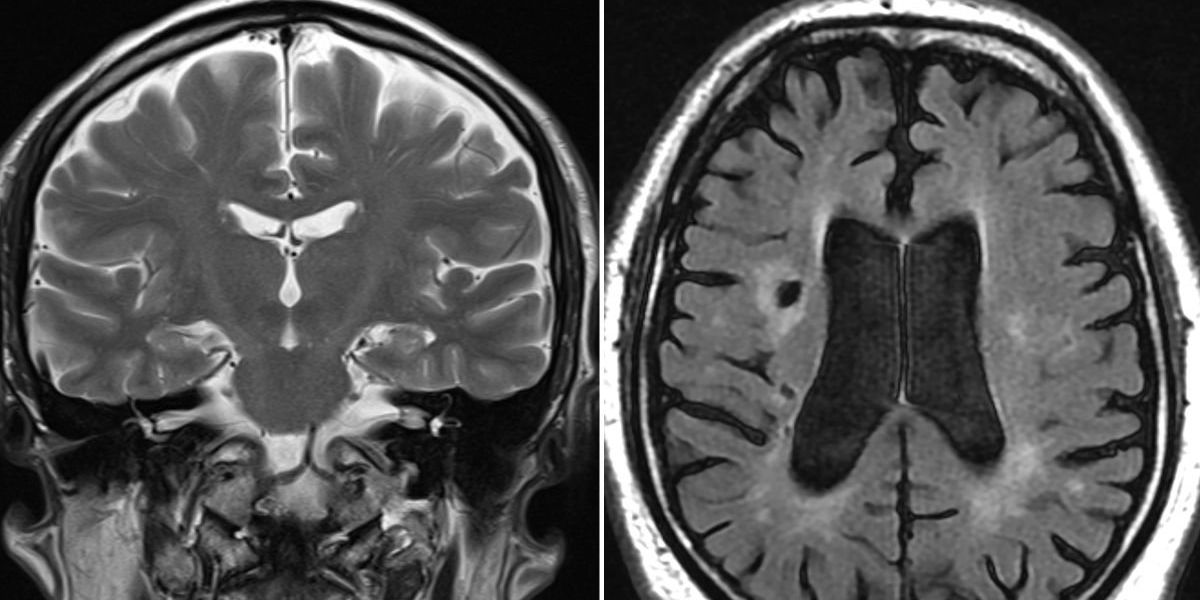

Gordon Robb, 63, from Bonnyrigg in Midlothian, experienced a brain bleed that left him unable to make sense of written words.

This particular symptom is incredibly rare. Specialists say that struggling to recognise written words alone, without any other signs, happens in fewer than 1 per cent of stroke patients.

When it comes to reading difficulties, as Mr Robb experienced, Lowe explains this happens when a small, specific area of the brain is affected, disrupting what experts call “higher executive functioning.”